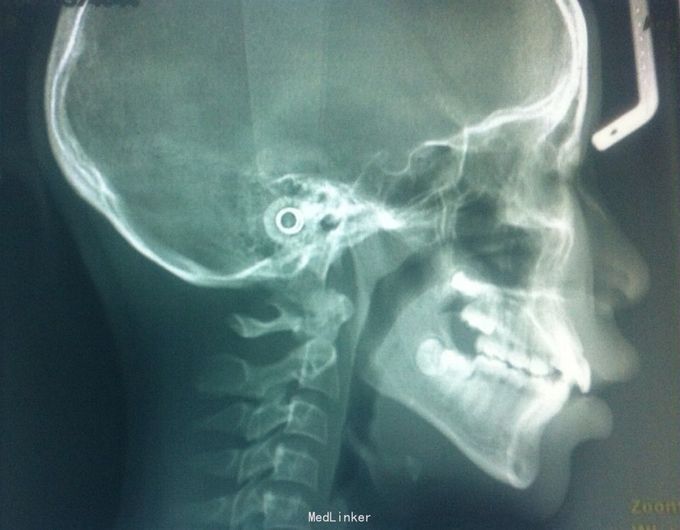

恒牙期 33,44唇侧错位 磨牙中性关系 前牙覆合2度、覆盖1度 牙列拥挤

牙列拥挤、安氏一类 拔牙矫治,拔除14、24、34、44(强支抗)排齐整平上下牙列,直丝弓矫治器,关闭拔牙间隙,矫治后前牙覆合覆盖正常,磨牙中性关系,面型略改善